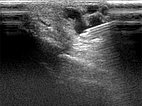

After embolization now clearly echogenic formations in the embolized vessel with dorsal acoustic shadowing due to the embolic agent after filling of the AVM nidus.